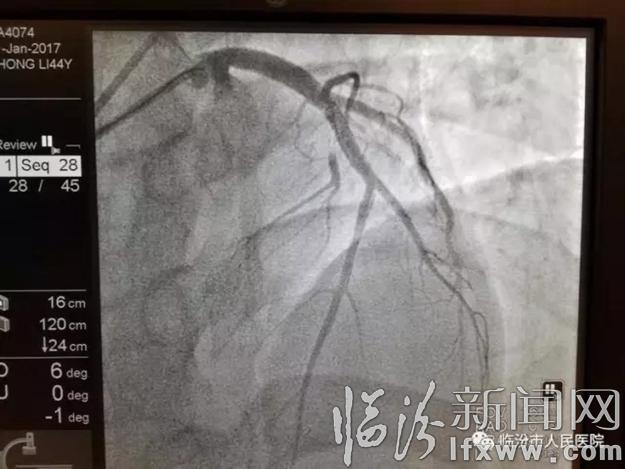

就在ICU紧张繁忙的同时,1月21日凌晨5点30分,我院心血管内科冷文俊、马琦及导管室团队也在第一导管室抢救一名急性前壁心肌梗死患者。该患者,男,44岁,主因持续胸痛2小时在侯马市人民医院诊断急性前壁心肌梗死,由于患者去年有脑出血病史,为静脉溶栓治疗的禁忌症,通过我院胸痛中心对接平台联系我院120紧急救援中心从侯马市人民医院转运,于转运至我院,心血管内科冷文俊、马琦及导管室团队给患者急诊冠状动脉造影提示前降支开口处100%闭塞,急诊开通前降支,置入支架1枚,术后前降支远段血流恢复,TIMI血流3级。患者情况基本稳定。